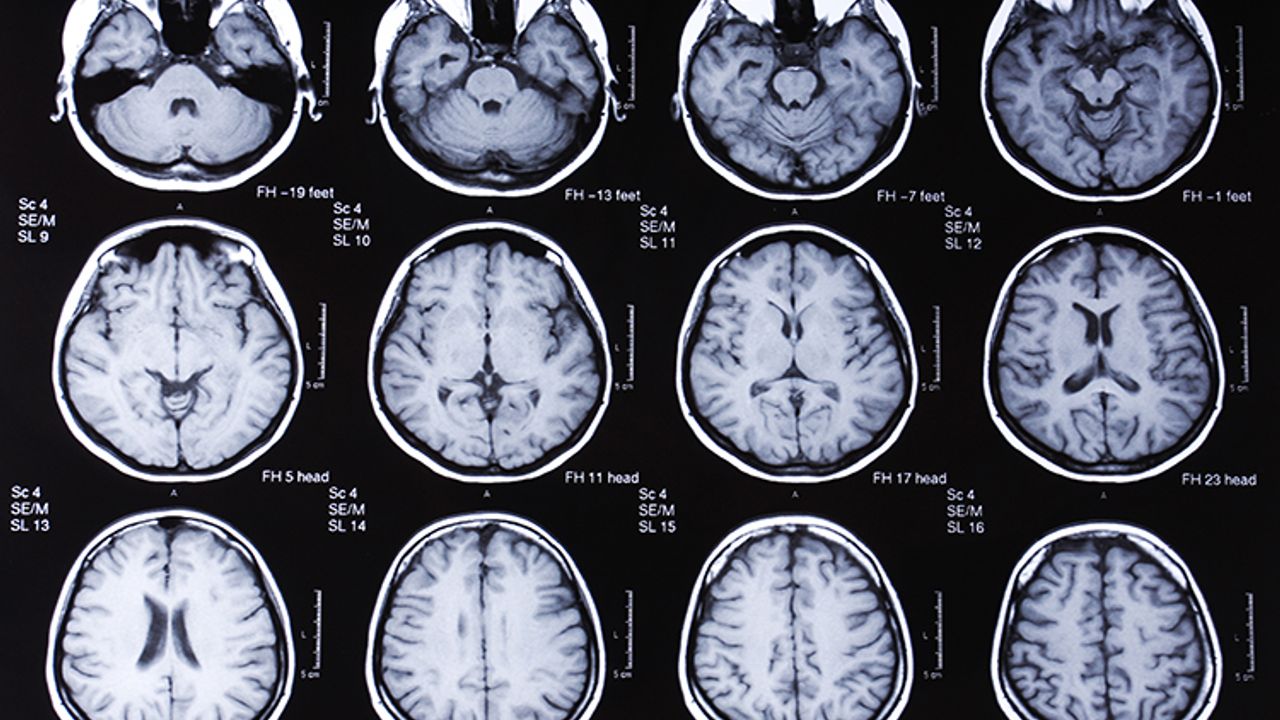

- Tanı genellikle nörolojik belirtiler ve beyin görüntülemeleriyle konulmaktadır. Kesin tanı, otopsi sonrası beyin dokusu incelemesi ile yapılabilmektedir.